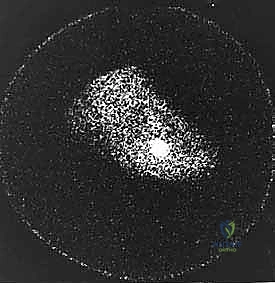

* Triple-Phase Bone Scan: Highly sensitive, it can demonstrate increased uptake in the tibial sesamoid region even before radiographic changes are evident, indicating metabolic activity consistent with injury or inflammation. Collimated views of the MTP joint are crucial.

Figure 5A: Triple-phase bone scan showing increased uptake in the tibial sesamoid region on an AP view of bilateral feet.

Figure 5B: Collimated view of the bone scan, clearly delineating the increased uptake in the tibial sesamoid.

Figure 5A: Another triple-phase bone scan image.

Figure 5B: Another collimated view from a triple-phase bone scan.